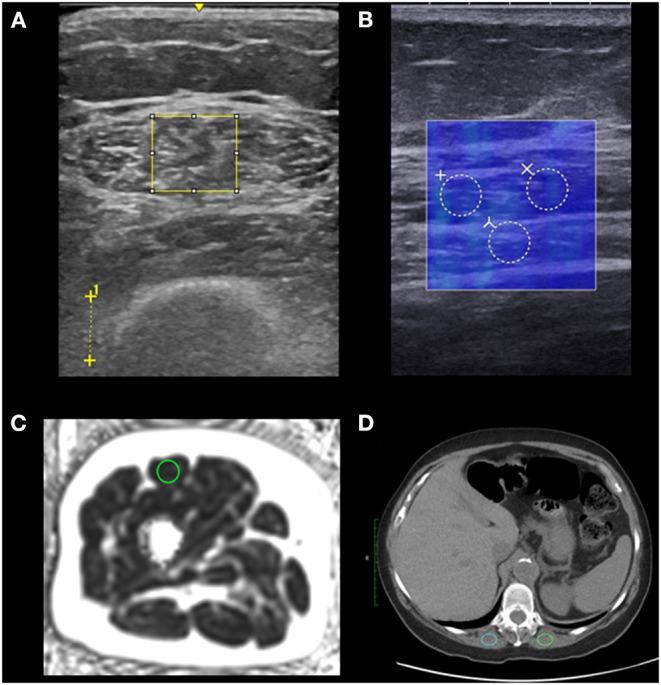

Establish bedside biomarkers of myosteatosis for sarcopenia and cachexia. We compared ultrasound biomarkers against MRI-based percent fat, histology, and CT-based muscle density among healthy adults and adults undergoing treatment for lung cancer.

METHODS

We compared ultrasound and MRI myosteatosis measures among young healthy, older healthy, and older adults with non-small cell lung cancer undergoing systemic treatment, all without significant medical concerns, in a cross-sectional pilot study. We assessed each participant's rectus femoris ultrasound-based echo intensity (EI), shear wave elastography-based shear wave speed, and MRI-based proton density fat-fraction (PDFF). We also assessed BMI, rectus femoris thickness and cross-sectional area. Rectus femoris biopsies were taken for all older adults ( = 20) and we analyzed chest CT scans for older adults undergoing treatment ( = 10). We determined associations between muscle assessments and BMI, and compared these assessments between groups.

RESULTS

A total of 10 young healthy adults, 10 older healthy adults, and 10 older adults undergoing treatment were recruited. PDFF was lower in young adults than in older healthy adults and older adults undergoing treatment (0.3 vs. 2.8 vs. 2.9%, respectively, = 0.01). Young adults had significantly lower EI than older healthy adults, but not older adults undergoing treatment (48.6 vs. 81.8 vs. 75.4, = 0.02). When comparing associations between measures, PDFF was strongly associated with EI (ρ = 0.75, < 0.01) and moderately negatively associated with shear wave speed (ρ = -0.49, < 0.01) but not BMI, whole leg cross-sectional area, or rectus femoris cross-sectional area. Among participants with CT scans, paraspinal muscle density was significantly associated with PDFF (ρ = -0.70, = 0.023). Histological markers of inflammation or degradation did not differ between older adult groups.

CONCLUSION

建立用于肌少症和恶病质的肌脂肪变性的床旁生物标志物。我们在健康成年人和接受肺癌治疗的成年人中,将超声生物标志物与基于磁共振成像(MRI)的脂肪百分比、组织学以及基于计算机断层扫描(CT)的肌肉密度进行了比较。

方法

在一项横断面试点研究中,我们比较了年轻健康、老年健康以及正在接受全身治疗的非小细胞肺癌老年患者的超声和MRI肌脂肪变性测量值,所有参与者均无重大医疗问题。我们评估了每位参与者基于股直肌超声的回声强度(EI)、基于剪切波弹性成像的剪切波速度以及基于MRI的质子密度脂肪分数(PDFF)。我们还评估了体重指数(BMI)、股直肌厚度和横截面积。对所有老年成年人(n = 20)进行了股直肌活检,并对接受治疗的老年成年人(n = 10)的胸部CT扫描进行了分析。我们确定了肌肉评估与BMI之间的关联,并比较了各组之间的这些评估。

结果

共招募了10名年轻健康成年人、10名老年健康成年人以及10名正在接受治疗的老年成年人。年轻成年人的PDFF低于老年健康成年人以及正在接受治疗的老年成年人(分别为0.3%、2.8%和2.9%,P = 0.01)。年轻成年人的EI显著低于老年健康成年人,但与正在接受治疗的老年成年人无差异(48.6、81.8和75.4,P = 0.02)。在比较测量值之间的关联时,PDFF与EI密切相关(ρ = √0.75,P < 0.01),与剪切波速度呈中度负相关(ρ = -0.49,P < 0.01),但与BMI、全腿横截面积或股直肌横截面积无关。在进行CT扫描的参与者中,椎旁肌密度与PDFF显著相关(ρ = -0.70,P = 0.023)。老年成年组之间炎症或降解的组织学标志物无差异。

结论

PDFF对年轻成年人与两个老年成年组之间的肌脂肪变性敏感。EI对组间肌脂肪变性的敏感性较低,但与PDFF密切相关,这与通常用于恶病质诊断的BMI不同。我们的结果表明,超声测量可能有助于在床旁确定肌脂肪变性,并且在诊断上比BMI等传统体重评估更有用。这些结果显示了将EI、剪切波速度和PDFF作为肌少症和恶病质的诊断和治疗生物标志物的前景。